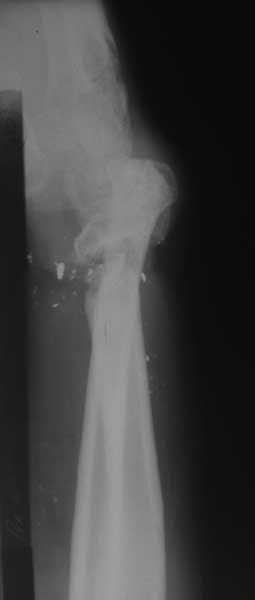

Вот дополнительные снимки

Мы предлагаем: Резекция ложного сустава в области дистального метаэпифиза лучевой кости. Артродез лучезапястного сустава. Пластика дефекта в области луча в типичном месте аутотрансплантантом из локтевой кости на сосудистой ножке. Остеосинтез пластиной. Укорочение локтевой кости. Остеосинтез пластиной.

Изучали ли вы достаточно тщательно ангиограммы пораженного сегмента? Если да, то вы обратили внимание, что в артериальной фазе практически полностью отсутствует контрастирование лучевой артерии в зоне дефекта, тем самым вы имеете разорванную артериальную дугу и стабильный кровоток только в одном бассейне-локтевой артерии, тыльная межкостная не контрастировалась. Невзирая на это, вы предлагаете использовать пластику дефекта трансплантатом локтевой кости на сосудистом пучке (единственном, который объективно сохранился). Не боитесь ли вы возникновения проблем кровоснабжения кисти при выполнении данного вмешательства и как вы готовы бороться с этим (имею в виду оснащение, специалистов по микрохирургии и пр.)-это вопрос номер 2.